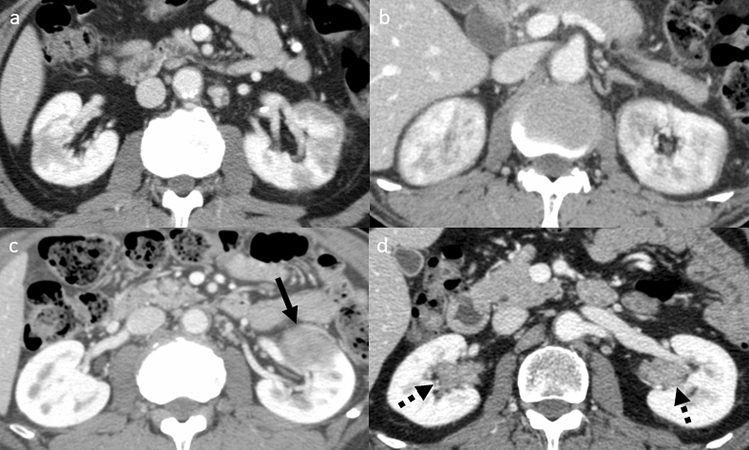

Based on the diagnostic criteria for IgG4-RKD10 and previous reports5,6,14,15, patients who had at least one of the following four imaging features on CE-CT were classified into the KD group: multiple hypodense lesions, diffuse renal swelling, a solitary hypodense lesion or diffuse thickening of the renal pelvis wall (Fig. 1). To evaluate renal function, the estimated glomerular filtration rate (eGFR) was calculated according to the serum creatinine levels in each patient. The eGFRs were classified from G1 to G5 based on the clinical practice guidelines for chronic kidney disease16, and the eGFRs at the initial diagnosis of AIP and the changes during the follow-up period were recorded. Those who had eGFR progression of two grades or more were considered to have exacerbation of renal function.

Figure 1.

Characteristic findings of IgG4-related kidney disease on contrast-enhanced CT. (a) Multiple hypodense lesions. (b) Diffuse renal swelling. (c) A solitary hypodense lesion (arrow). (d) Diffuse thickening of the renal pelvis wall (broken arrows).